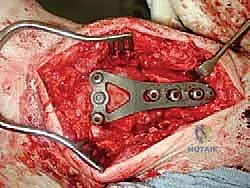

علاج هذه الكسور يتطلب مهارة فائقة من الدكتور محمد هطيف، حيث يتم استخدام تقنيات الجراحة الميكروسكوبية وتثبيت الكسور باستخدام صفائح معدنية دقيقة ومسامير (Locking Plates) دون المساس بثبات المفصل الصناعي، أو يتم دمج علاج الكسر ضمن عملية مراجعة المفصل الكلية إذا كان المفصل نفسه تالفاً.

تعتبر غرفة العمليات ساحة لإظهار البراعة الجراحية. عملية المراجعة تستغرق عادة من 3 إلى 5 ساعات وتتم عبر الخطوات المعقدة التالية:

يتم فتح الشق الجراحي الأمامي القديم بحذر شديد لتجنب إتلاف الأوعية الدموية والأعصاب، وهنا تبرز أهمية تقنيات الجراحة الميكروسكوبية التي يتقنها الدكتور هطيف.

الخطوة الثالثة: إزالة المفصل القديم (Explant Removal)

يتم استخراج المكونات المعدنية والبلاستيكية لمفصل (Agility) القديم بحرص بالغ للحفاظ على ما تبقى من العظم السليم.

الخطوة الرابعة: تنظيف العظم والترقيع (Debridement and Bone Grafting)

يتم تنظيف الأنسجة الملتهبة والأكياس العظمية. ونظراً لأن مفصل (Agility) يترك فراغاً كبيراً بعد إزالته، يتم استخدام طعوم عظمية (Autograft من حوض المريض أو Allograft من بنك العظام) لملء الفراغات وبناء أساس قوي.

الخطوة الخامسة: تركيب المفصل الجديد أو الدمج

يتم إدخال المفصل الجديد المخصص للمراجعة، والذي يحتوي غالباً على سيقان (Stems) تدخل عميقاً في عظمة الساق وعظمة الكاحل لضمان الثبات الميكانيكي. في حال وجود كسور في الكعب، يتم تثبيتها في هذه المرحلة.

الخطوة السادسة: الإغلاق التجميلي

يتم خياطة الأربطة والأنسجة الرخوة والجلد بطرق تجميلية دقيقة لتقليل الندبات وسرعة الالتئام، ثم توضع القدم في جبيرة خلفية واقية.